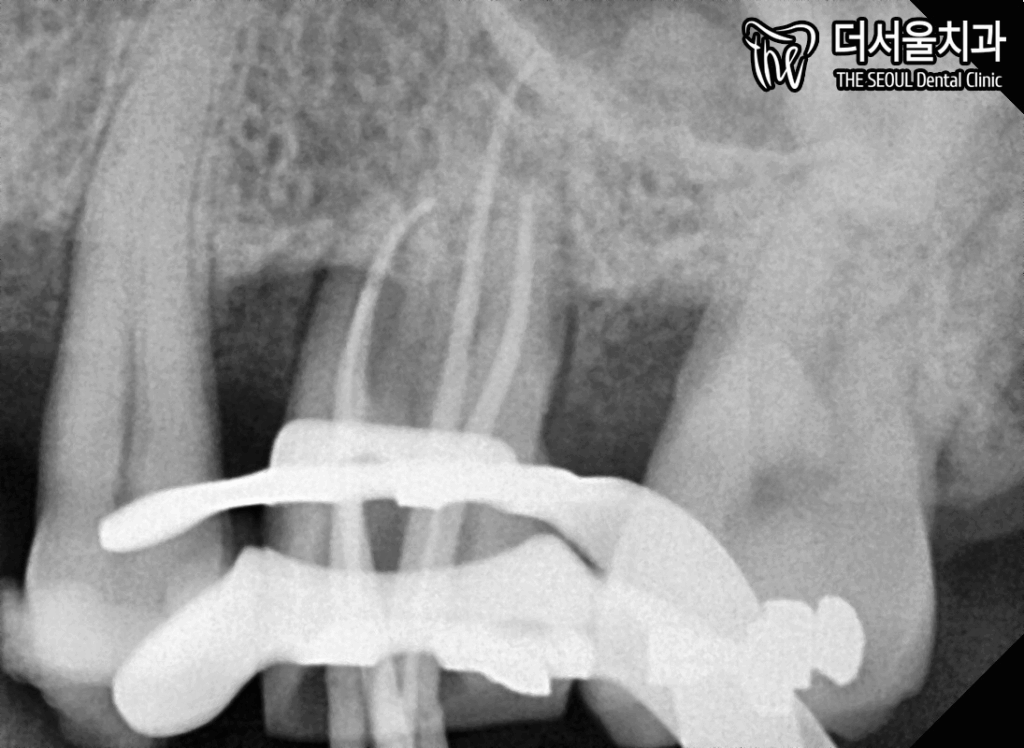

다음은 인접면 충치 소견이 있던

26번 어금니 신경치료를 해줍니다.

인접면에서 파고 들면

그만큼 더 빠르게 침투합니다.

때문에 치수까지 감염되어서

신경치료를 하게 되었던 겁니다.

성남 치과 의원은

꼼꼼히 내부 감염 조직을 제거하고

재감염이 일어나지 않도록

소독 및 세척을 해줍니다.

이후, 코어 작업 및 인상 채득을 진행합니다.